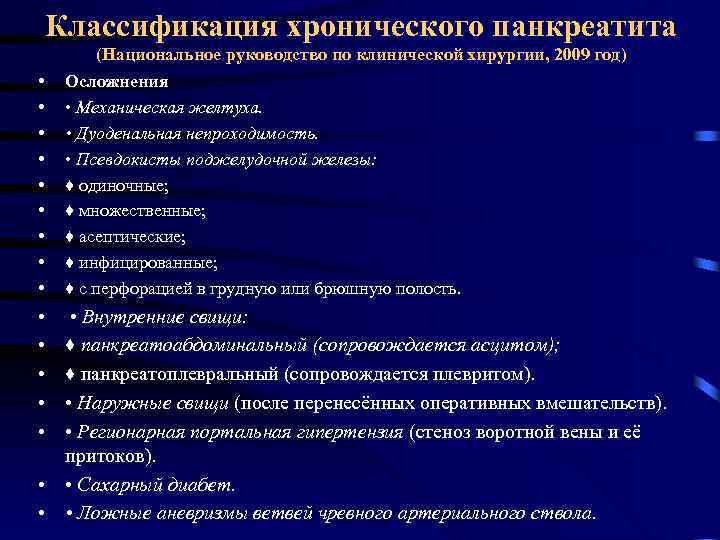

Классификация хронического панкреатита • • • (Национальное руководство по клинической хирургии, 2009 год) Осложнения • Механическая желтуха. • Дуоденальная непроходимость. • Псевдокисты поджелудочной железы: ♦ одиночные; ♦ множественные; ♦ асептические; ♦ инфицированные; ♦ с перфорацией в грудную или брюшную полость. • • Внутренние свищи: • • ♦ панкреатоабдоминальный (сопровождается асцитом); ♦ панкреатоплевральный (сопровождается плевритом). • Наружные свищи (после перенесённых оперативных вмешательств). • Регионарная портальная гипертензия (стеноз воротной вены и её притоков). • • Сахарный диабет. • • Ложные аневризмы ветвей чревного артериального ствола.